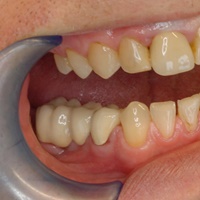

Odbudowa kosci wyrostka zębodołowego żuchwy, odbudowa dziąsła, wydłużenie koron klinicznych górnych przedtrzonowców, implantacja.